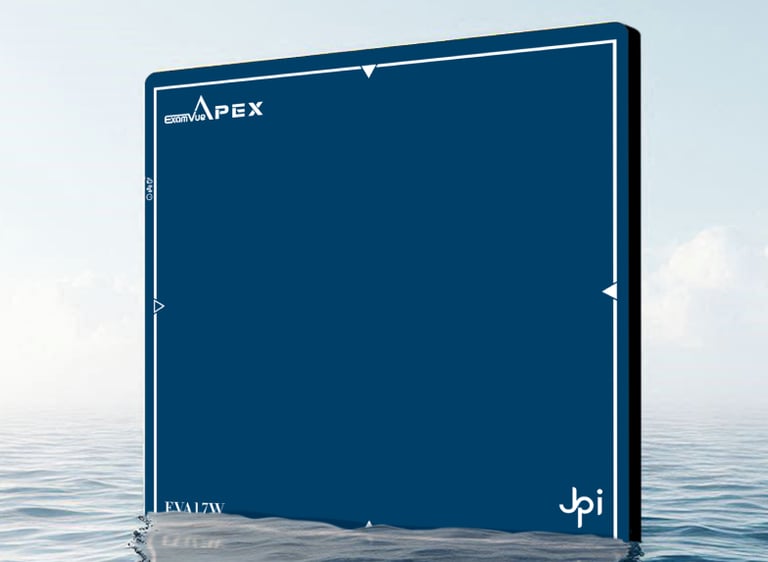

Diseñado para optimizar la captura de imágenes radiográficas con la más alta calidad y eficiencia

DRE DUO

Detector digital de rayos X portátil con doble panel para captura rápida y precisa de imágenes radiológicas.

Diseñado para optimizar la captura de imágenes radiográficas con la más alta calidad y eficiencia